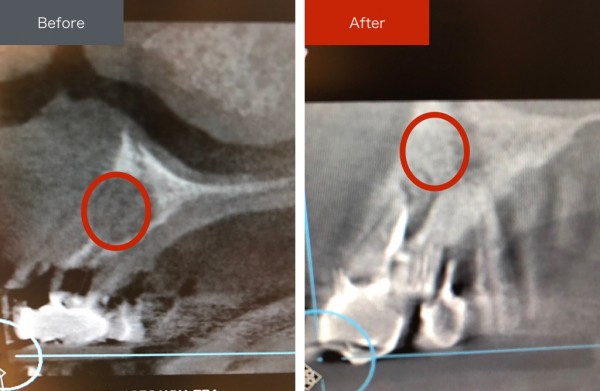

Case003 – 精密根管治療

精密根管治療の症例です。

感染によって骨がなくなってしまっていたため、温存はかなり難しい症例でしたが、根管治療によって骨も再生して完治しました。

根の治療は「とりあえず痛みを取ること」を目的とするのではなく、完治させ、このように骨の再生も促し、延命ではなく「一生使えるような歯にする」ことを目的としています。

誰が何をしても残せない歯については抜くしかありませんが、きちんとした治療をすることで残せる可能性のある歯については全力で残せるように治療してまいります。

担当:理事長 佐藤悠野